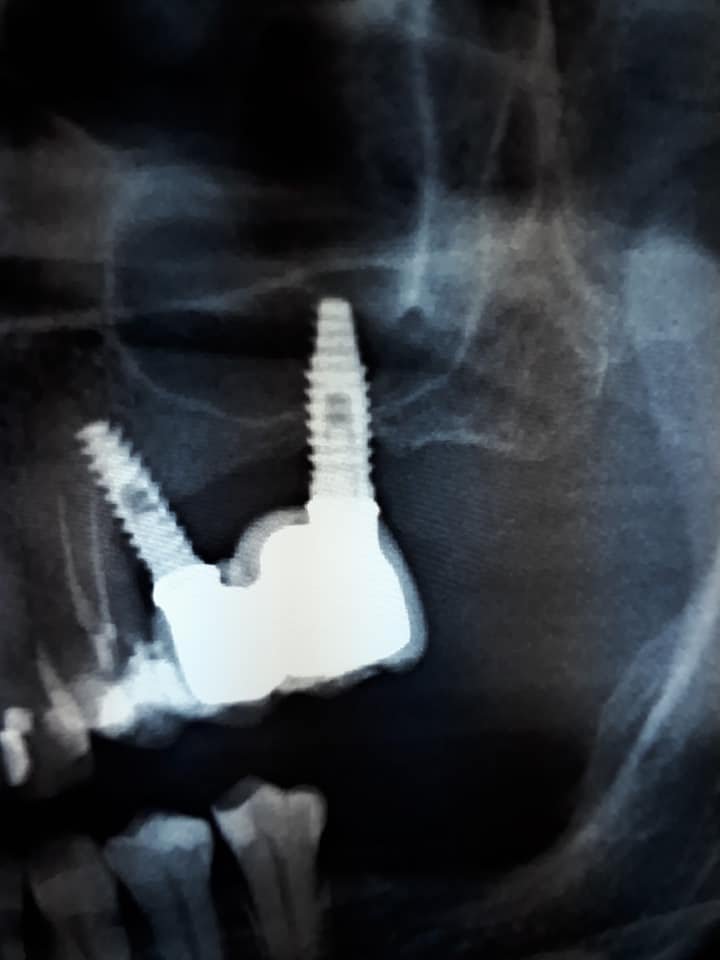

hola, quisiera saber tipo de implante,marca...

Ayuda con este Implante